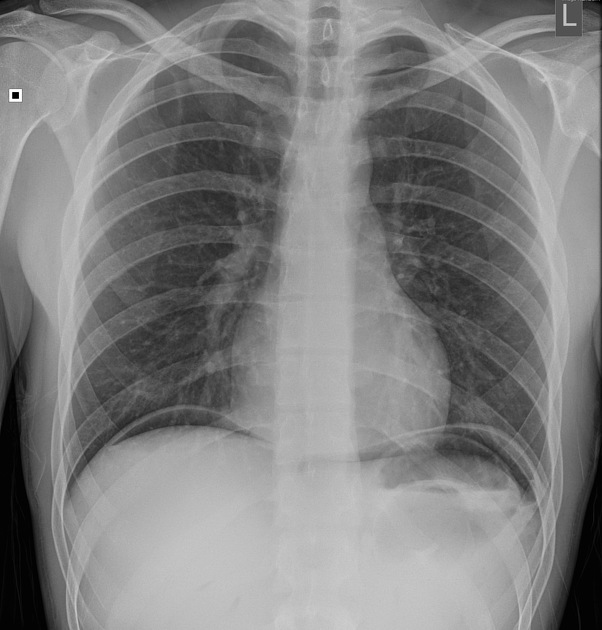

Describe the abnormality demonstrated.

Right-sided pneumothorax